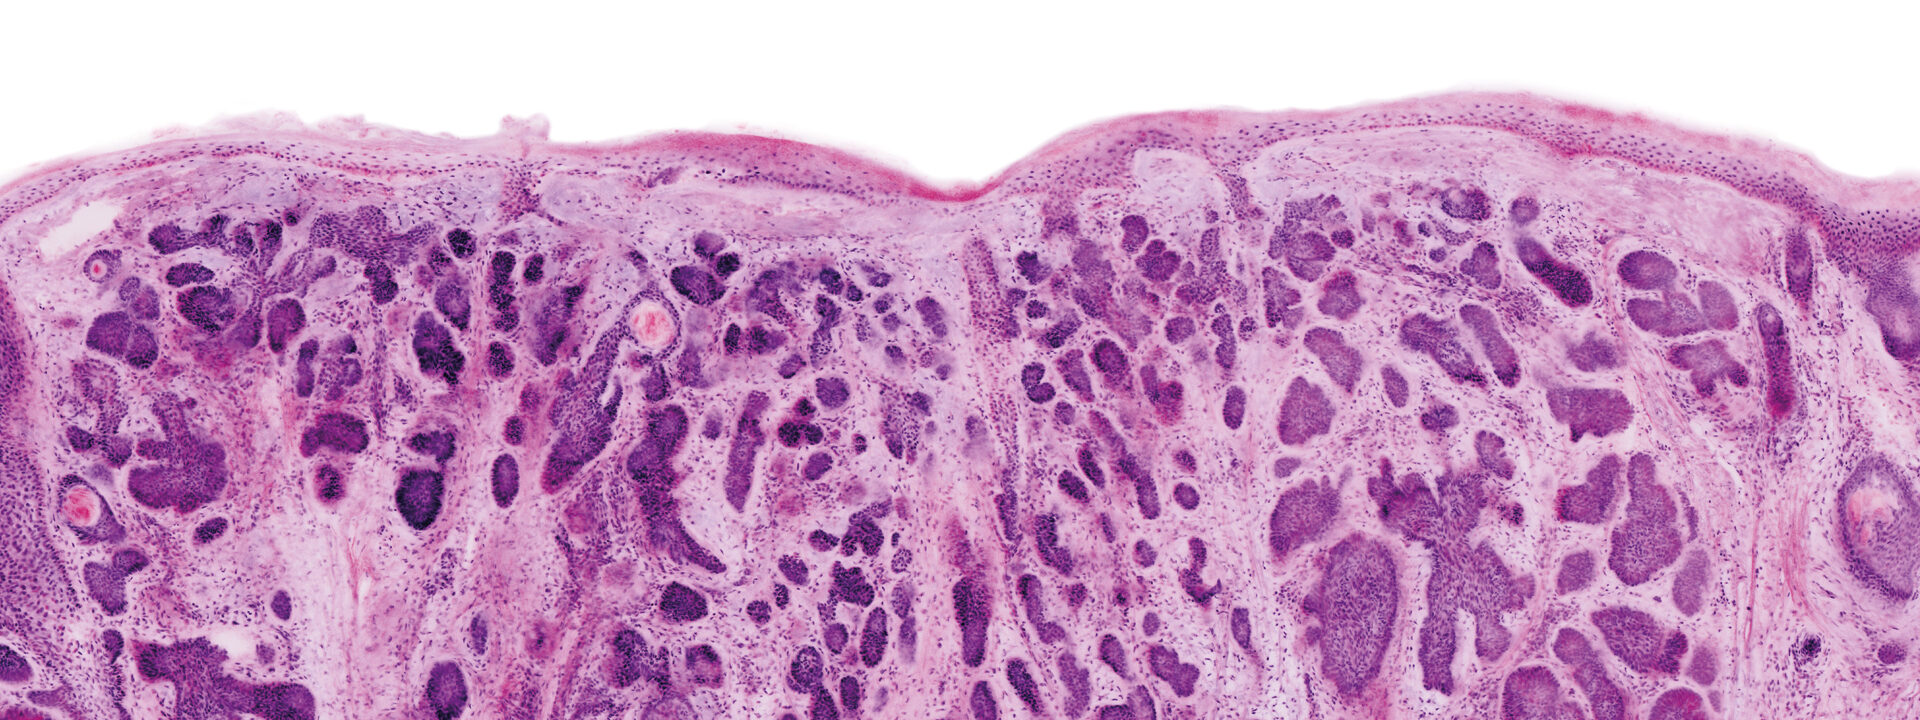

Images courtesy of Dr Javiera Pérez-Anker.

Basal cell carcinoma; imaged with the VivaScope 2500 (left) and after H&E staining (right)